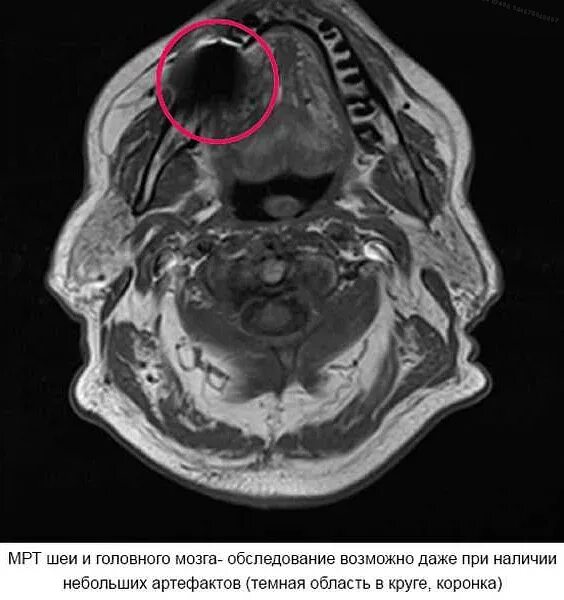

Что можно сделать если нельзя эмрт